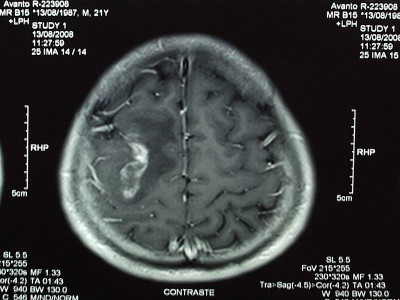

.

Casos Neuroloquirúrgicos

Envíado por Dr. Ruben Eduardo Amaya Contreras